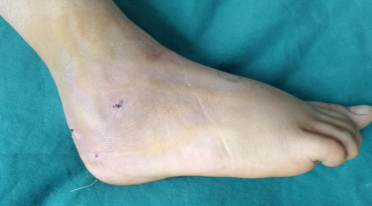

术后第5天,孩子恢复良好,几乎看不见伤口。

“踝关节镜手术的特点,是微创小切口,患者创伤小,消肿时间短,恢复时间快,术后并发症少,避免了大切口手术可能导致的伤口感染、瘢痕挛缩、皮瓣坏死等风险。”徐明亮主任说。 术后一周,小吉出院回家康复。